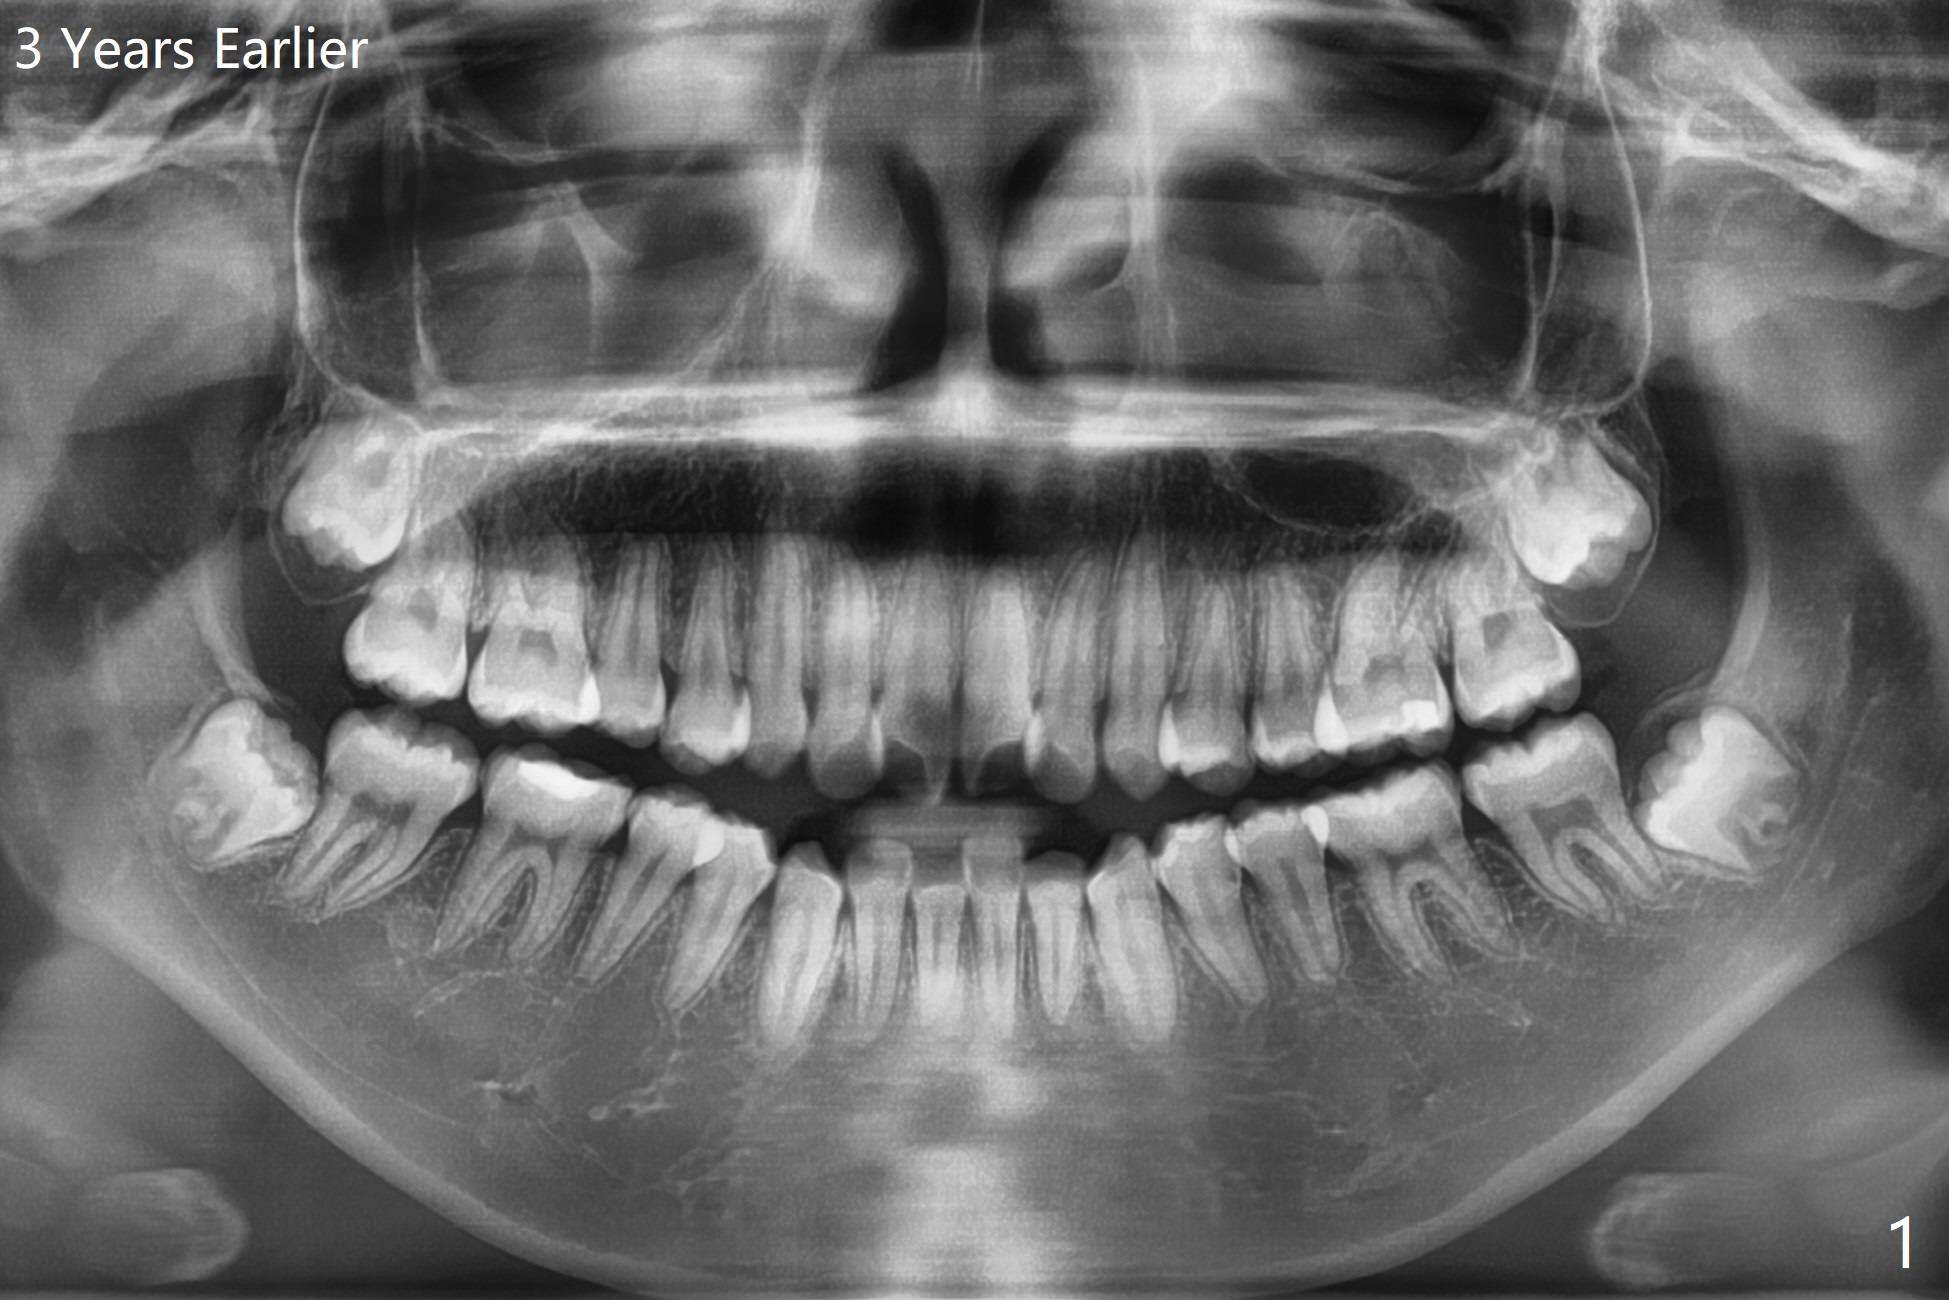

17岁女孩3年前拍摄全景片后拔除4个第一双尖牙(图一),在别的诊所进行矫正(图二,三),在局麻下拔除4个智齿,由于去骨,显得外斜嵴缺失(图四:箭头),放置胶原塞(防止干槽症),4-0含铬羊肠线缝合,预计外斜嵴6-12月能修复。